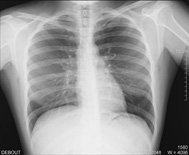

| des poumons en cas de toux